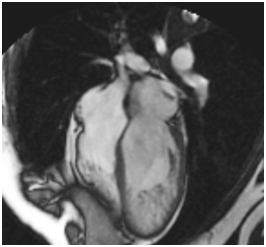

All 38 patients had a diagnosis of LV non-compaction on cardiac MRI, using criteria of non-compacted/compacted myocardium > 2.5 to 1.0 and deep LV trabeculations. During development, the heart muscle is a sponge-like network of muscle fibers. Eur J Echocardiogr 08;.

These pieces of muscles are called trabeculations. Echo-cardiography and black blood cardiac MRI images may show thickened myocardium without trabeculations corresponding to areas of noncompaction. Left ventricular noncompaction 2.

Although echocardiography has been the diagnostic test of choice for noncompaction, other modalities have been used for the diagnosis, including contrast ventriculography, ,21 computed tomography, 16,21 and MRI. The following are key points to remember from this report on a multicenter retrospective study from the Netherlands that analyzed patients with noncompaction cardiomyopathy (NCCM). Blinded reviews of echocardiograms measured (1) depths of intertrabecular recesses (X/Y), (2) noncompaction-to-compaction ratio (NC/C), and (3) number of trabeculations, using a segmental approach.

Contrast-enhanced echo-cardiography and cine SSFP imaging are fundamental to a correct differential diagnosis because they can depict myocardial trabeculations corresponding to areas characterized by myocardial thickening. Left ventricular noncompaction 1. The ability to acquire LVNC is supported by case reports and studies demonstrating increased LV trabeculation developing on serial echocardiographic assessment (9–11).

3 The clinical diagnosis is predominantly reliant on three. Echocardiography is the standard tool for diagnosis, and CMR is very useful to confirm or rule out this disease, especially when the apex is difficult to visualise. 9:306–308 Google Scholar 49.

15,25,26 MRI provides good correlation with echo for localization and extent of noncompaction and is useful in cases with poor. Echoes from 100 patients, of which 51 had received the diagnosis of LV non-compaction (NC), were reviewed. Prominent left ventric-ular (LV) trabeculae, deep intertrabecular recesses, and the thin compacted layer (1).The spectrum of morphologic variability is extreme, ranging from hearts with a nearly absent compacted layer and an almost exclusively trabecular compo-.